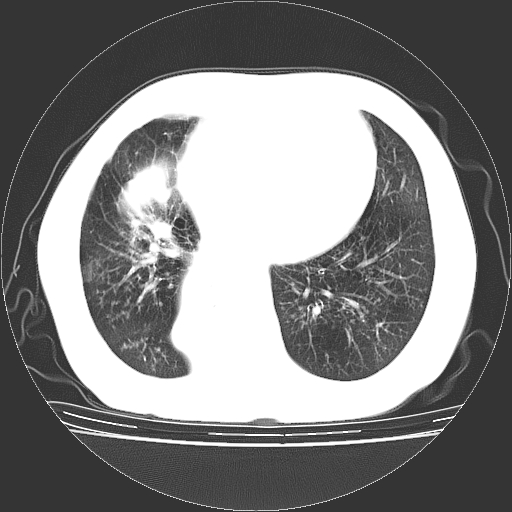

女,70岁,咳嗽、咳痰一个月,低热一周。

1.左上肺结核,部分纤维化。右肺中下叶部分肺不张,内见液化、坏死及点状钙化,右中下叶支气管壁增厚、管腔狭窄,见多个点状钙化,结合临床考虑支气管内膜结核,建议痰检查抗酸杆菌并参考血沉。两肺多个小圆点状高密度灶,境界模糊,多考虑结核肺内播散。但本人年龄较大首先应支气管镜检以除外右肺癌。

一元论:内膜结核伴下肺阻塞性肺炎并双肺播散!另:主动脉夹层。右侧少量胸腔积液。